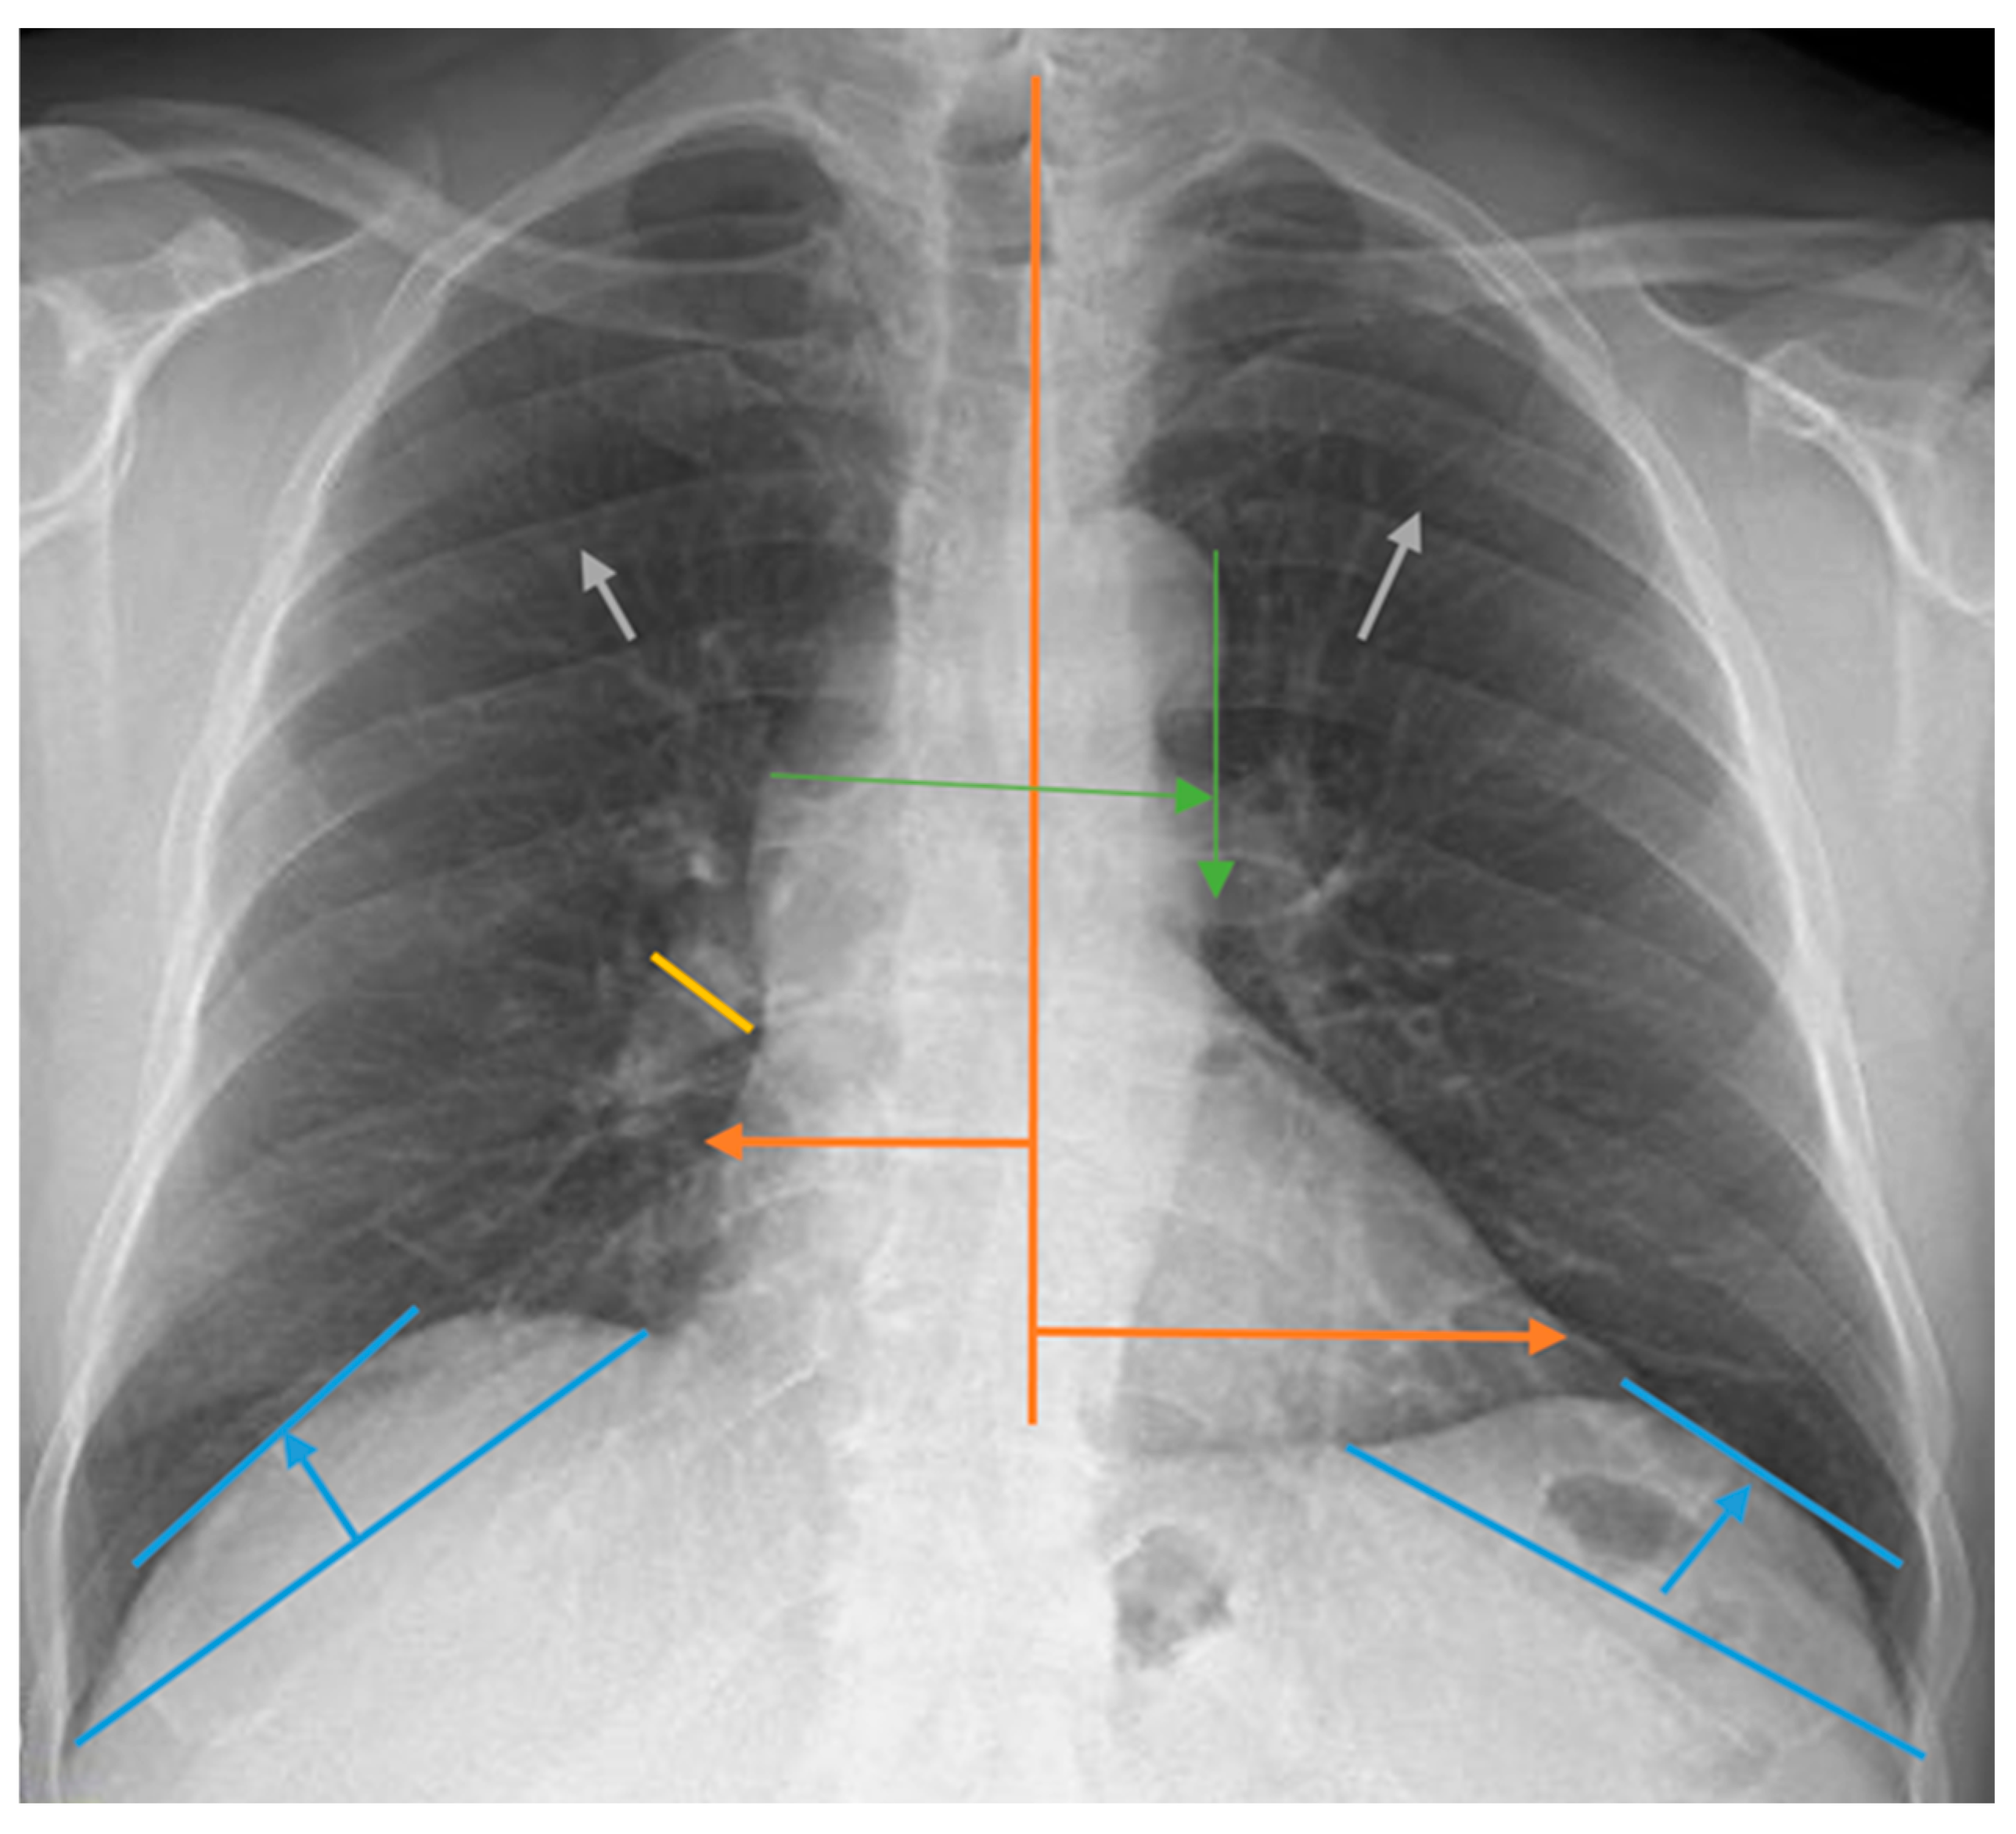

2.2. Lung Radiograph Measurement Calculations